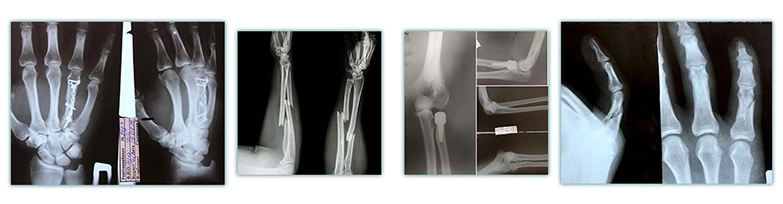

К специалисту обращаются в основном после травм

(например, после повреждений сухожилий опасным инструментом

или глубоких порезов ножом при приготовлении пищи),

а также при переломах, в том числе для установки

металлических фиксирующих конструкций или их удаления.